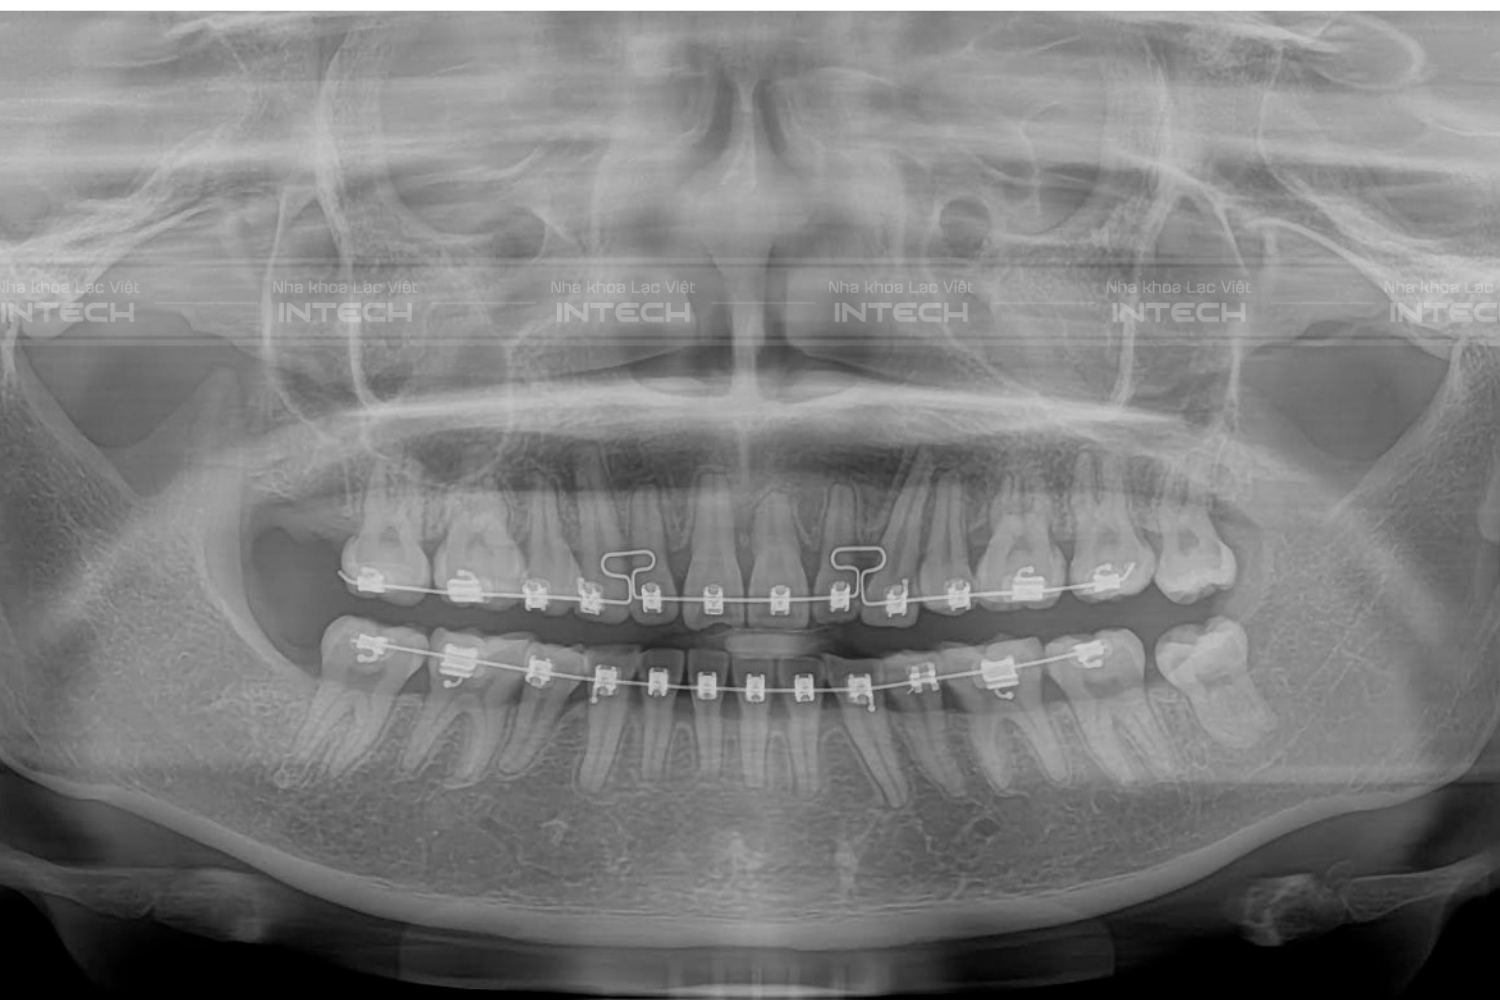

Nguyên nhân dẫn tới loại biến chứng niềng răng này chủ yếu do nha sĩ dùng lực quá mạnh, làm thiếu máu cục bộ vùng chóp răng hoặc sử dụng sai khí cụ khiến chóp chân răng đi ra khỏi xương ổ răng, dẫn tới tiêu ngót chân răng. Việc quan sát được mình có bị tiêu chóp chân răng không hề đơn giản vì đây là biến chứng nằm sâu trong ổ răng mà chỉ có phim X-Quang 3D mới có thể xác định được.

Trên tay bác sĩ đang là tình trạng một bạn khách hàng niềng răng hỏng TẠI Hải Phòng và đến với Lạc Việt Intech với tình trạng tiêu chóp chân răng. Trên hình ảnh này bác sĩ thấy những dấu hiệu cho việc này như: ..... Đây chính là những dấu hiệu trực quan nhất cho biến chứng niềng răng này.

Cũng giống như tiêu chóp chân răng, việc quan sát được mình có bị tiêu xương tụt lợi hay không không hề đơn giản vì đây là biến chứng nằm ở xương mà chỉ có phim X-Quang 3D mới có thể xác định được. Trên tay bác sĩ đang là tình trạng một bạn khách hàng niềng răng hỏng và đến với Lạc Việt Intech với tình trạng tiêu xương ổ răng.